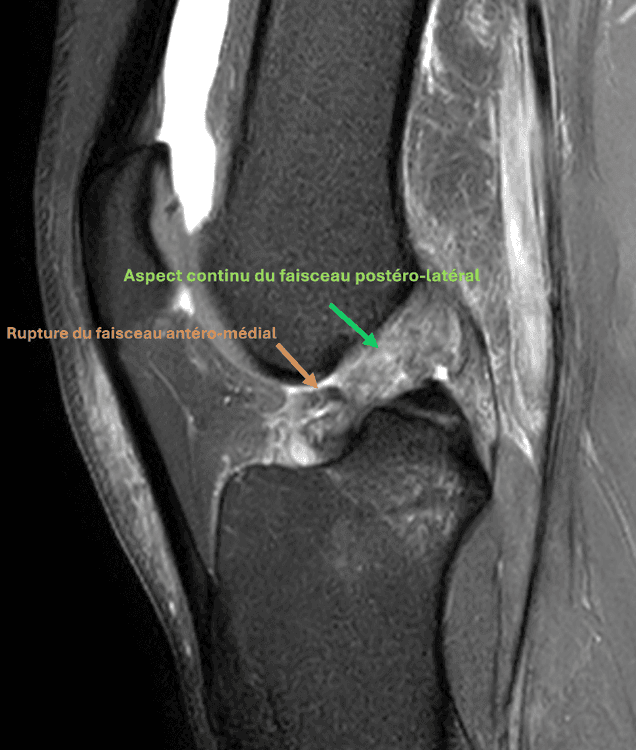

Rupture partielle du ligament croisé antérieur aux dépens du faisceau antéro-médial, avec aspect continu du faisceau postéro-latéral.

MRI